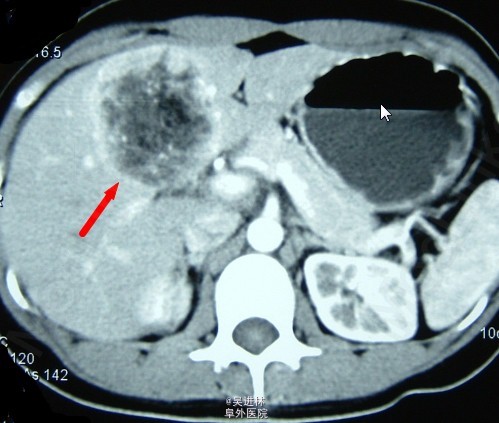

肝血管平滑肌脂肪瘤是一种含脂肪组织的肝脏良性肿瘤,包括平滑肌、血管及成熟型脂肪细胞三种组织学成分。临床无明显症状。据搜狗百科介绍,到目前为止世界文献共报道29例!!本例患者男,45岁,为体检发现肝区占位就诊。